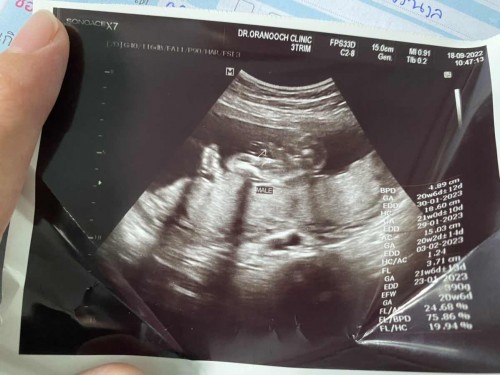

แม่ดูไม่ออกเลย หมอว่าเป็นผู้ชาย แม่ๆเห็นกันไหมคะ

ตรงปลายลูกศรชี้ จู๋น้องชัดมากค่ะแม่ 😁

ที่ลูกศรชี้จู๋น้องค่ะ ชัดมากๆ

ที่ลูกศรชี้คือช้างน้อยค่ะแม่

ได้ผู้ชายคะMALE แปลว่าผู้ชาย